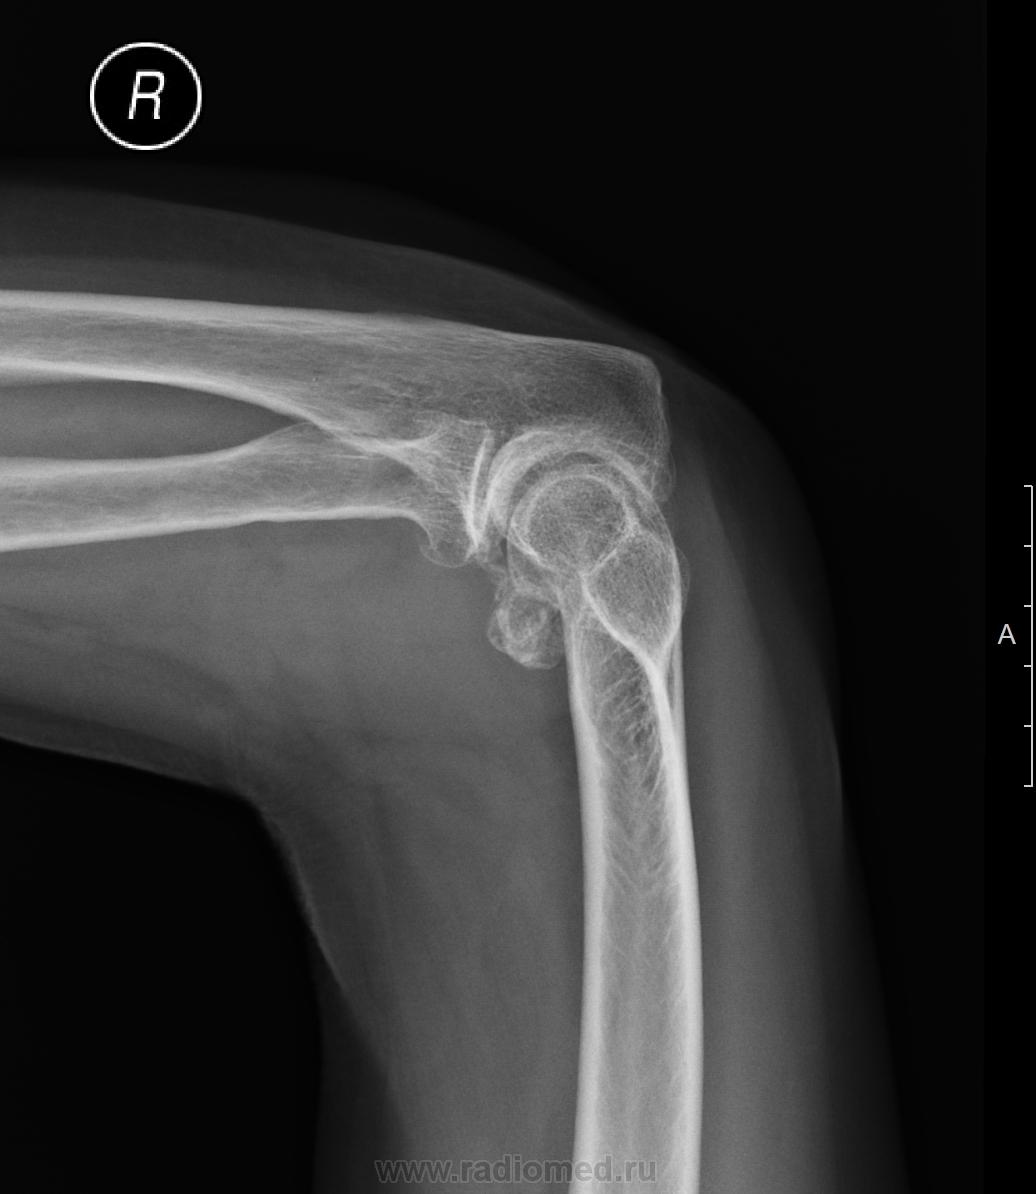

Пол пациента: Женский пол Тип патологии: Метаболическое заболевание Область исследования: Скелетно-мышечная система Методы исследования: Rg Какая природа участка обызвествления в параартикулярных тканях? Может быть ли вызвать травма такое изменение? https://radiomed.ru/sites/default/files/styles/case_slider_image/public/user/19785/f_elbow_20140324_170729.jpg?itok=088WJYc_ ID:36367 Mon, 24/03/2014 - 17:04 #1 ren_gen Offline Last seen: 11 years 6 months ago Joined: 30.10.2010 - 19:17 Posts: 285 это все что у вас есть? снимок в боковой проекции перевернутый вверх ногами?! Mon, 24/03/2014 - 17:11 #2 перчик Offline Last seen: 6 months 2 days ago Joined: 06.03.2014 - 12:16 Posts: 721 Пардон)) добавил еще проекцию Mon, 24/03/2014 - 20:43 #3 И.Бондаренко Offline Last seen: 2 days 21 hours ago Joined: 13.09.2011 - 22:55 Posts: 9214 Написал бы хондроматоз. Mon, 24/03/2014 - 21:10 #4 Дмитрий Волегов Offline Last seen: 3 years 11 months ago Joined: 22.05.2013 - 00:32 Posts: 1148 перчик wrote: Какая природа участка обызвествления в параартикулярных тканях? Трудно сказать. Природа затемнения - обызвествление. Обызвествляться может, наверное, всё. Но чаще хрящевая ткань. Может постравматический артроз. перчик wrote: Может быть ли вызвать травма такое изменение? Может. Старая травма. С Уважением, Дмитрий.

Написал бы хондроматоз.

Трудно сказать. Природа затемнения - обызвествление. Обызвествляться может, наверное, всё. Но чаще хрящевая ткань.

Может постравматический артроз.

Может. Старая травма.